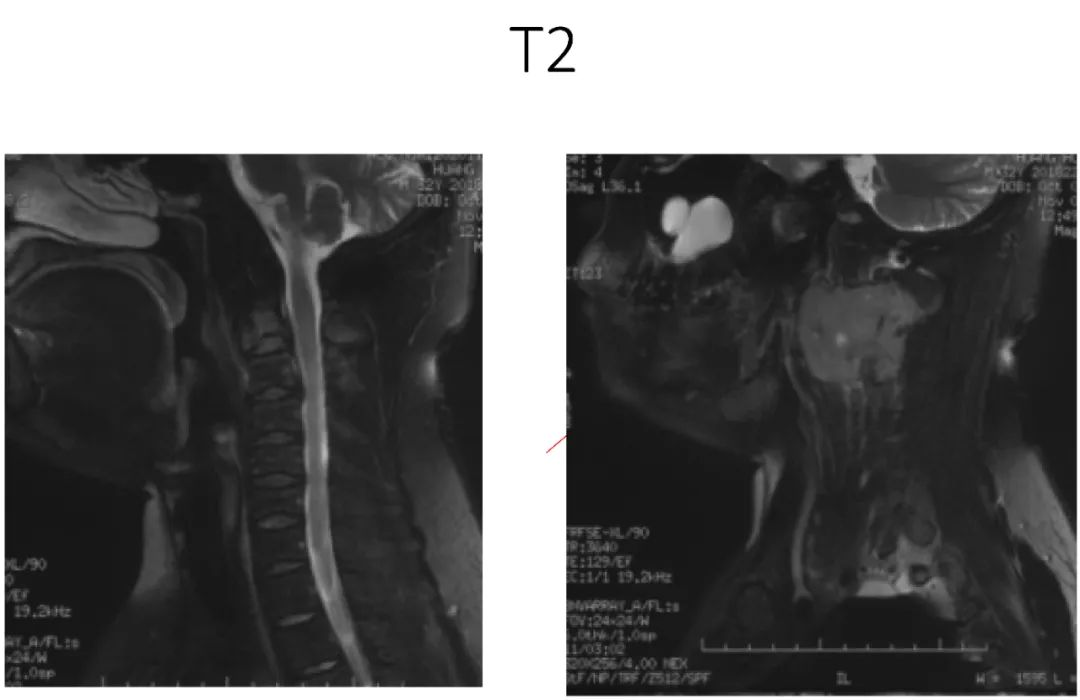

病史:male, 63 y/o

Neck pain for 3 months

影像资料:

诊断:C2椎体肿瘤